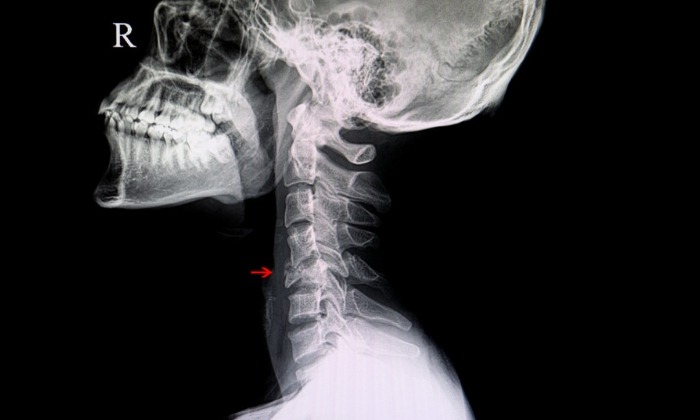

กระดูกคอประกอบด้วยกระดูกต่างๆ ทั้งหมด 7 ชิ้น ทำหน้าที่พยุงศีรษะ และเชื่อมระหว่างศีรษะกับไหล่และร่างกาย การหักหรือการแตกที่กระดูกคอชิ้นใดชิ้นหนึ่ง หรือกระดูกคอหัก (Cervical fracture) มักเรียกว่าคอหัก (broken neck)

หากคอได้รับบาดเจ็บ คุณไม่ควรเคลื่อนไหวคอหรืออวัยวะส่วนที่เกี่ยวข้อง จนกว่าจะมีการตรวจเอ็กซเรย์ หากผู้ป่วยหมดสติ แพทย์จะเป็นผู้สันนิษฐานว่า ผู้ป่วยที่หมดสติมีอาการบาดเจ็บที่คอหรือไม่ แล้วค่อยดำเนินการรักษาตามสถานการณ์ต่อไป

ผู้ป่วยที่ได้รับบาดเจ็บที่คอแบบเฉียบพลัน และยังคงรู้สึกตัว อาจมีปวดคอรุนแรง หรืออาจไม่มีเลยก็ได้ ผู้ป่วยบางรายอาจมีอาการปวดที่ลุกลามจากคอไปยังไหล่หรือแขน ซึ่งเกิดจากกระดูกสันหลังกดทับเส้นประสาท และอาจมีแผลฟกช้ำและอาการบวมบริเวณด้านหลังคอ โดยแพทย์จะทำการตรวจทางประสาทวิทยาโดยละเอียดเพื่อประเมินการทำงานของเส้นประสาท และอาจให้มีการตรวจเอ็มอาร์ไอ (MRI) หรือการตรวจซีทีสแกน (CT scan) เพิ่มเติม เพื่อตรวจหาความรุนแรงของอาการบาดเจ็บ